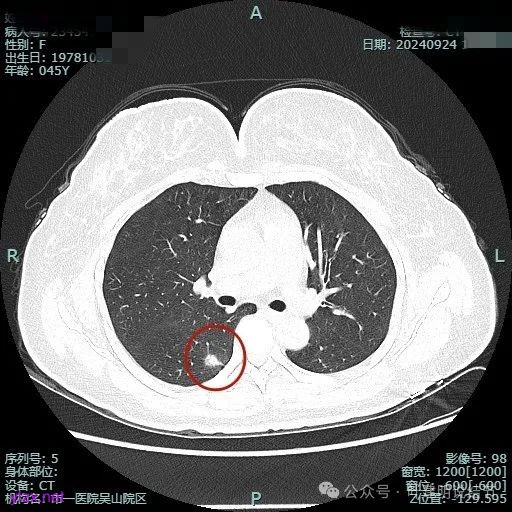

我们先来看2024年9月时的影像:

病灶1:

病灶是混合密度,边缘少许淡磨玻璃,灶内不太致密,表面不平,血管征有,但说不上明显异常增粗。

病灶紧贴叶间裂,而且感觉跨过肺叶,部分影响到上叶了,病灶本身密度虽实性为主,但是不太致密,有点松散的感觉。

总体实性部分密度较高,而磨玻璃部分密度较低,且瘤肺边界欠清,关键是跨叶间裂生长,这与肿瘤似乎不容易解释些。

毛刺有但不太锐利,磨玻璃有但偏淡,实性为但不太致密,叶间裂与之关系密切,病灶跨叶生长。

上图显得与肿瘤较为符合,但跨叶生长的话,侵袭力应该较强,可她这病灶较刚发现时进展并不太明显。

上图层面也较符合恶性,血管进入明显,有浅分叶的样子,整体觉得有一定收缩力与膨胀感。

病灶表面不平,混合密度,磨玻璃成分较淡。